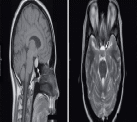

Магнитно-резонансная томография. Наиболее информативный метод исследования гипофиза. При магнитно-резонансной томографии визуализируются передняя и задняя доли, воронка гипофиза, возможно оценить симметричность гипофиза, положение воронки, состояние спинки турецкого седла. На МР-сканах структура аденогипофиза гомогенная, изоинтенсивна с белым веществом мозга.

Аденомы гипофиза на Т1 ВИ – визуализируются как зоны со сниженным по сравнению с остальной тканью аденогипофиза сигналом, на Т2ВИ – как зоны с повышенным сигналом. При внутривенном контрастировании аденомы накапливают контрастное вещество и можно более детально оценить структуру опухоли.

Рисунок Магнитно-резонансные томограммы головного мозга: а) коронарная плоскость; б) сагиттальная плоскость. Гипофиз (возрастная норма).

Рисунок Магнитно-резонансная томограмма гипофиза и области турецкого седла: 1 – лобная доля; 2 – мозолистое тело; 3 – боковой желудочек; 4 – мозжечок; 5 – гипофиз; 6 – клиновидная пазуха.